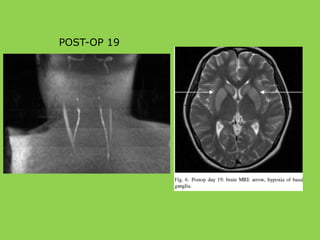

POST-OP 1

POST-OP 19

POST-OP 2 MONTHS

• Color Doppler– left internal carotid flow

POST-OP 2 MONTHS CONCLUSION •Congenital hypoplasia internal carotid